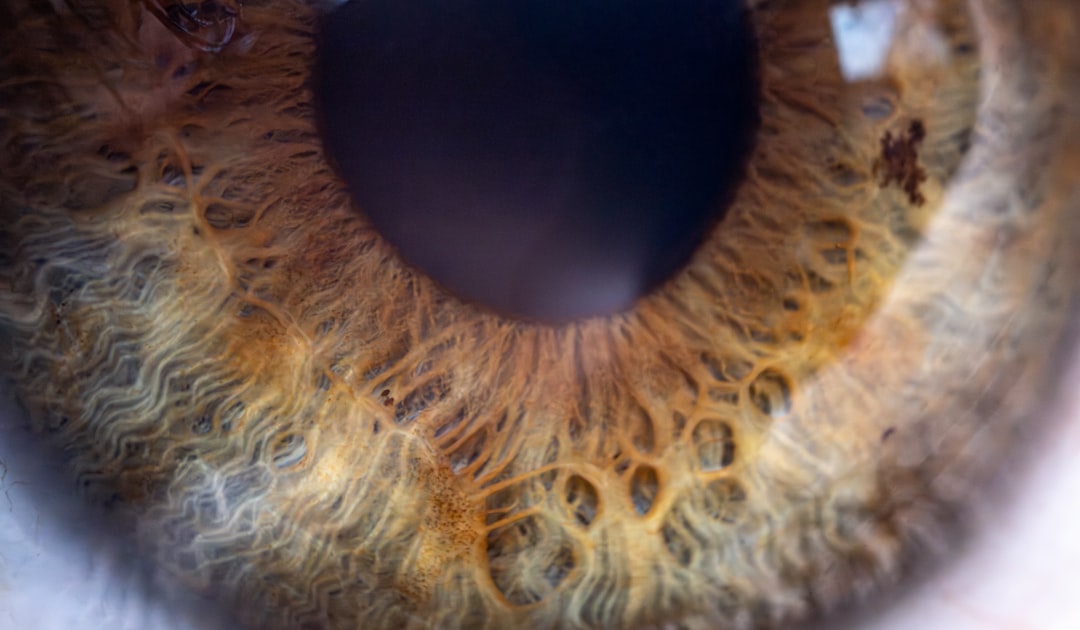

백내장 수술 비용은 시술을 받기 위해 필요한 비용을 의미합니다. 백내장이라고 하면 대개 노화에 의해 렌즈가 흐려지는 현상을 설명합니다. 이러한 경우 수술을 통해 시력을 회복할 수 있습니다. 그런데, 많은 분들이 걱정하는 것이 백내장 수술 비용입니다. 예상보다 높은 비용이 발생할 경우, 경제적인 부담이 될 수 있기 때문에 미리 비용에 대한 정보를 아는 것이 중요합니다.